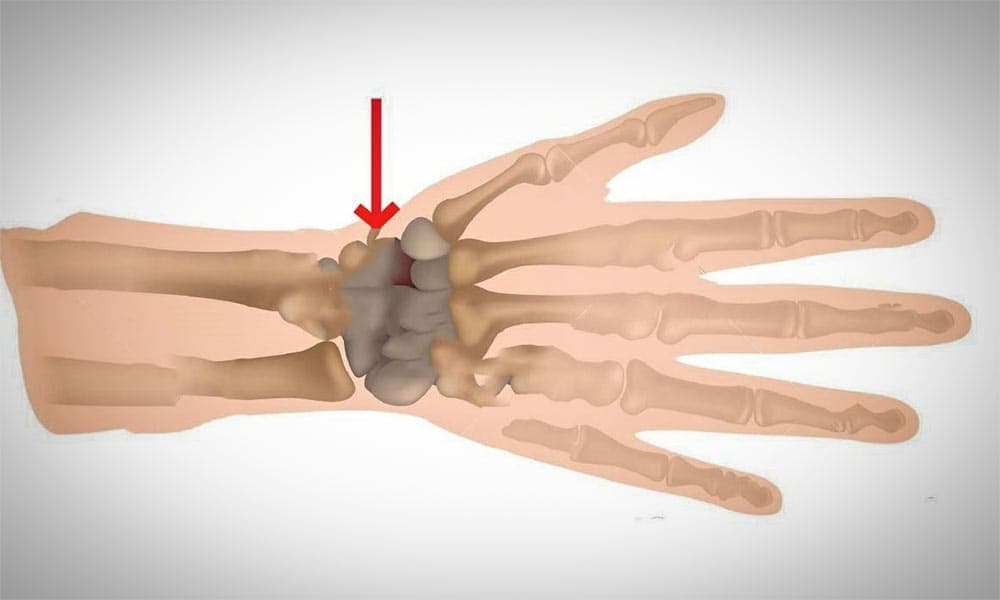

Kienböck Hastalığı Nedir?

Kienböck hastalığı el bileğinde bulunan lunat kemiğin avasküler nekrozu ve bunun sebep olduğu el bileği sorunları...